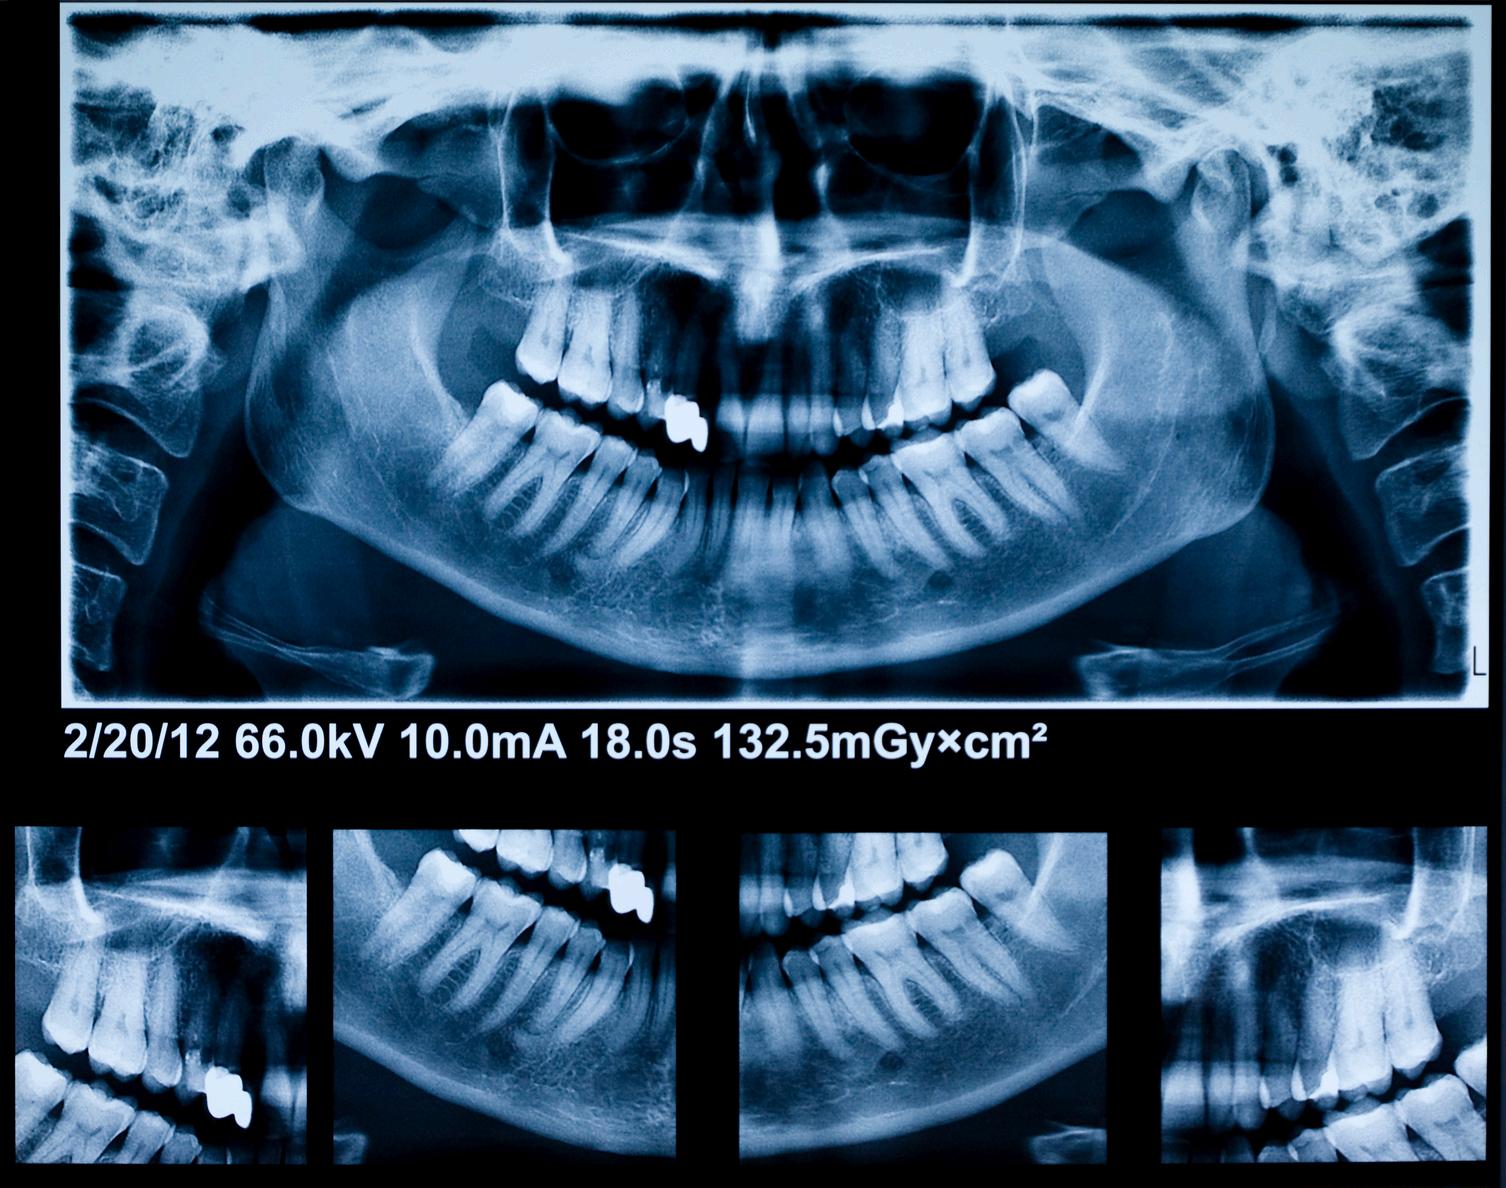

El quiste de retención mucoso del seno maxilar es una lesión benigna, generalmente asintomática, que se detecta de manera incidental en estudios radiográficos. Se presenta el caso de un paciente en el que, durante una radiografía panorámica de rutina, se identificó una imagen radiopaca bien delimitada en seno maxilar izquierdo compatible con quiste de retención mucoso Se discuten las características radiográficas, el diagnóstico diferencial y las consideraciones clínicas en el manejo de este hallazgo

Reporte de caso

Paciente masculino, de 35 años, acude para valoración odontológica general Se realizó radiografía panorámica como parte del examen inicial En el seno maxilar izquierdo se observó una imagen radiopaca de límites definidos, redondeada, localizada en la pared inferior del seno No se observaron signos de destrucción ósea ni desplazamiento de estructuras adyacentes

El paciente no refirió síntomas respiratorios ni dolor en la región. Con base en las características radiográficas, el hallazgo fue diagnosticado como quiste de retención mucoso en seno maxilar izquierdo. Se indicó control clínico y tomografía, al no requerir tratamiento quirúrgico inmediato.

Introducción

El QRM es una entidad benigna, autolimitada y habitualmente asintomática. Radiográficamente se presenta como una opacidad homogénea, redondeada, en el interior del seno maxilar, sin comprometer la arquitectura ósea.

El diagnóstico diferencial incluye sinusitis crónica, pólipos antrales y lesiones quísticas odontogénicas que invaden el seno Sin embargo, la ausencia de sintomatología y la apariencia radiográfica típica orientan hacia un QRM

La mayoría de los casos no requiere tratamiento, siendo suficiente el seguimiento clínico-radiográfico